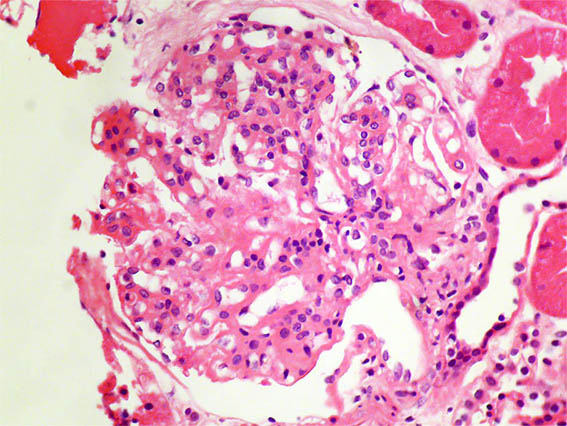

Figure 2. H&E, X400.